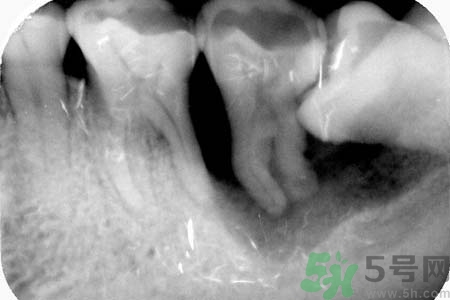

針對(duì)長(zhǎng)歪了的智齒,專家建議及早的拔智齒處理,至于拔智齒多少錢,一般來說拔智齒多少錢在150—300元左右,具體根據(jù)智齒的拔除難易程度而定,如果智齒阻生較為嚴(yán)重的話,在拔智齒前還需要拍x光片以了解智齒及鄰牙的具體結(jié)構(gòu),這種情況下,拔智齒多少錢相對(duì)要貴一些。